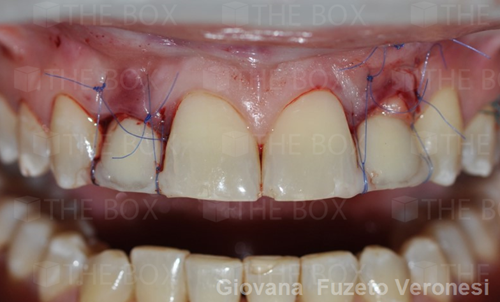

Infra bony defect one wall defect follow up 18 months show regeneration of buccal bone and interdental defect utilizing allograft bone substitute